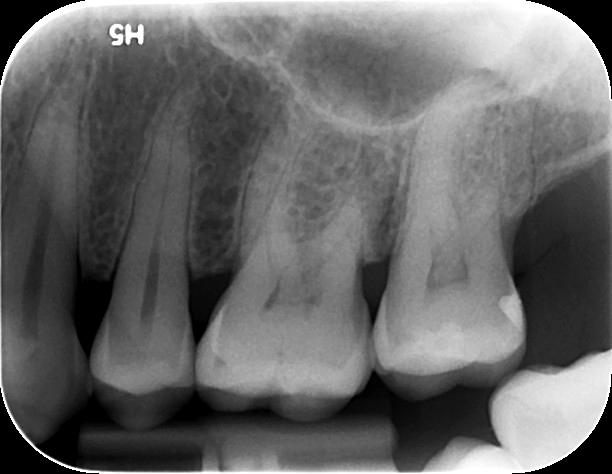

Η οπισθοφατνιακή ακτινογραφία λαμβάνεται με την τοποθέτηση του ακτινογραφικού πλακιδίου εσωτερικά των δοντιών (προς την πλευρά της γλώσσας ή του ουρανίσκου) και παράλληλα με αυτά. Χρησιμοποιείται ειδικός συγκρατητήρας του φιλμ, τον οποίο δαγκώνει ο εξεταζόμενος. Με αυτή απεικονίζονται ένα ή περισσότερα δόντια (τόσο η μύλη, όσο και η ρίζα αυτών), καθώς και τμήμα του φατνιακού οστού που περιβάλλει τις ρίζες των δοντιών. Αποτελεί την πιο απλή οδοντιατρική ακτινογραφική απεικόνιση. Χρησιμοποιούνται τρία μεγέθη φιλμ ή πλακιδίου ανάλογα με την περιοχή που θέλουμε να απεικονιστεί, το μέγεθος του στόματος του εξεταζόμενου και την ηλικία του. Η λήψη της είναι γρήγορη (διαρκεί λίγα δευτερόλεπτα) και ανώδυνη.

Η οπισθοφατνιακή ακτινογραφία μεταξύ άλλων μας επιτρέπει:

• την ανίχνευση οδοντικών τερηδόνων, τον καθορισμό της έκτασης και του βάθους τους και της σχέσης τους με τον πολφό του δοντιού

• τη μελέτη των ριζών των δοντιών (αριθμός, μορφολογία και πιθανή κάμψη αυτών, ύπαρξη απορρόφησης ή κατάγματος)

• τη μελέτη του αριθμού, της μορφολογίας, του εύρους και της πορείας των ριζικών σωλήνων εντός των ριζών

• τη μελέτη των σκληρών ιστών του περιοδοντίου, δηλαδή του φατνιακού οστού που περιβάλλει και στηρίζει το δόντι και του περιοδοντικού συνδέσμου. Σε περίπτωση περιοδοντικής νόσου, καθορίζεται η εντόπιση, ο βαθμός και η φύση (οριζόντια, γωνιώδης) της απορρόφησης του φατνιακού οστού

• τη μελέτη του φατνιακού οστού της περιακρορριζικής περιοχής του δοντιού για ύπαρξη παθολογικών εξεργασιών (απόστημα, κοκκίωμα, κύστη κ.λ.π.)

• την ανίχνευση κατάγματος των δοντιών.